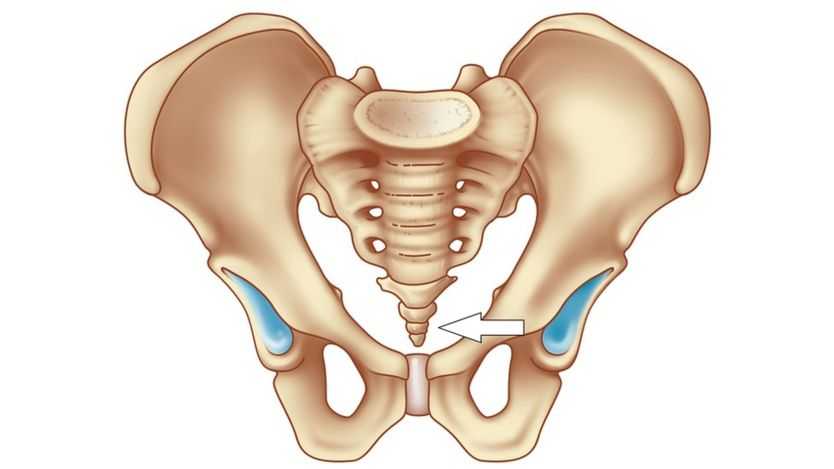

Копчик

представляет нижний отдел позвоночника, включающий нескольких сросшихся позвонков. Функция переднего отдела органа служит для крепления связок и мышц.

Благодаря ему происходит правильная, равномерная нагрузка на таз. Копчик является примером рудимента хвоста у современного человека, служившего центром равновесия.

Например, копчик одновременно выполняет несколько предназначений — к нему крепятся:

- мышцы и связки, участвующие в функционировании мочеполовой системы и отдаленных отделов толстого кишечника;

- часть большой ягодичной мышцы, отвечающей за разгибание бедра;

- с его помощью правильно распределяется физическая нагрузка на таз.

Это нижний отдел позвоночника, который состоит из трех или пяти сросшихся позвонков. Он представляет собой не что иное, как наш рудиментарный хвост. Несмотря на рудиментарный характер, копчик является довольно важным органом (как и другие рудименты, которые, хоть и утратили большую часть своего функционала, все еще остаются весьма полезными для нашего организма).

Передние отделы копчика необходимы для прикрепления мышц и связок, которые участвуют в функционировании органов мочеполовой системы и дистальных отделов толстого кишечника (к ним крепятся копчиковая, подвздошно-копчиковая и лобково-копчиковая мышцы, которые формируют мышцу, поднимающую задний проход, а также заднепроходно-копчиковая связка). Помимо того, к копчику прикрепляется часть мышечных пучков большой ягодичной мышцы, которая отвечает за разгибание бедра. А еще копчик нужен нам для того, чтобы правильно распределять физическую нагрузку на таз.